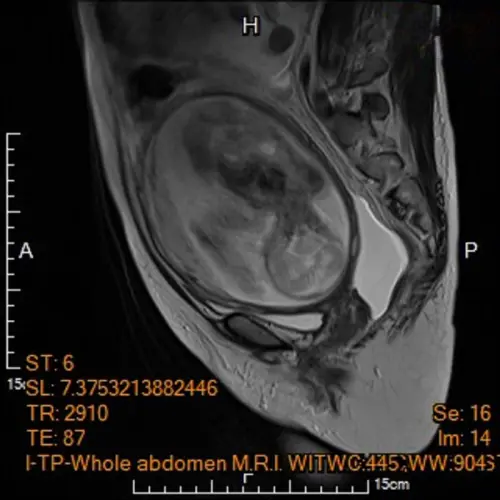

▲電腦斷層顯示子宮內胎兒。(圖/馬偕紀念醫院) 李小姐在懷孕中發現惡性腫瘤,在前往其他醫院諮詢後,他院給予立即進行手術切除腫瘤,甚至可能一併移除子宮,導致無法保全胎兒等一連串大規模的處置。為了給自己與孩子更多的機會,馬偕紀念醫院高危險妊娠照護團隊遂決定會診婦癌科主任陳楨瑞尋找可能的診斷與手術治療方式。

一名懷孕5個月的孕婦,在例行性產檢意外發現卵巢有惡性腫瘤,馬偕紀念醫院高危險妊娠科資深主治醫師王亮凱表示,李小姐腹中胎兒發育情況一切正常,但超音波檢查意外發現孕婦腹腔內積滿大量腹水,及左側下腹部有一個15公分大小、邊界模糊、結構複雜的卵巢腫瘤,孕婦反映有明顯的進食與呼吸困難疑似腸胃道問題,為求謹慎,針對腹水檢體進行細胞檢驗,雖未能於腹水內發現癌細胞,腹部核磁共振影像顯示腫瘤疑似來自左側卵巢,且惡性風險極高,高度懷疑是懷孕中合併卵巢癌。